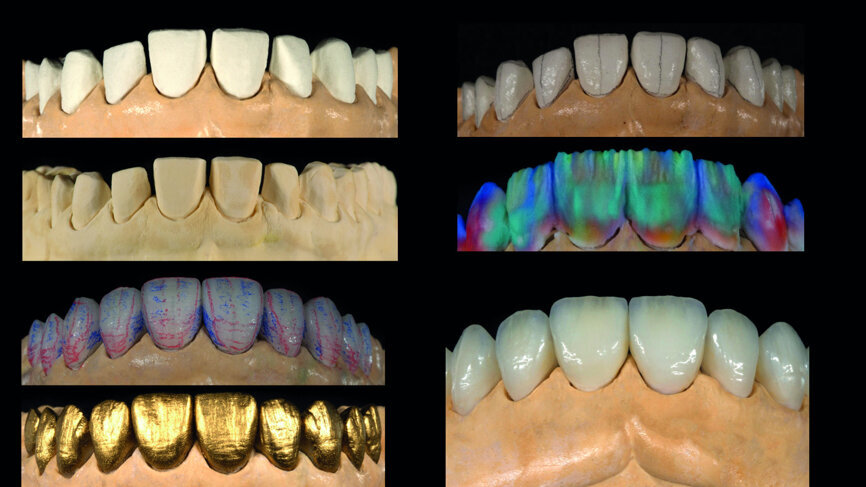

Fig. 14: Digital workflow (3-D printed model, CAD/CAM veneers, adjustments, staining/glazing).

Provisionalisation was executed digitally, using Telio CAD (Ivoclar Vivadent) in the Wieland Select CNC milling machine. The design was performed with the 3Shape DentalDesigner 2015 software (Figs. 12a & b). Two sets of final restorations were fabricated. The set of feldspathic veneers was fabricated on a stone model using IPS Style (Ivoclar Vivadent), while IPS Empress CAD Multi (Ivoclar Vivadent) was used for the digitalset (Figs. 13 & 14). Both sets were examined intraorally with a try-in paste to compare the optical properties of the feldspathic and the CAD/CAM veneers (Figs. 15a–c).

Intraoral digital scanning is a perfect alternative clinical procedure compared with the conventional impression technique. The digital planning and mock-up procedure is a powerful communication tool for the dentist, although special skills in using computer software are required. Regarding the laboratory workflow, most of the analogue procedures require more time (refractory dies, built-up veneers, adjustments), except the staining/glazing (Figs. 18a & b). Although the aesthetic outcome of the feldspathic veneers was subjectively chosen in this case, the analogue workflow is much more demanding. The digital approach, because of the reduced difficulty, speed, complexity and patient discomfort, tends to be preferable (Figs. 18a & b).